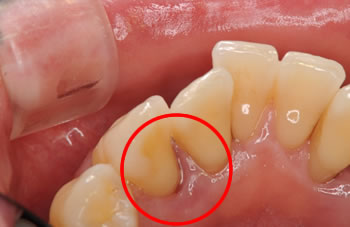

■治療前

出血と排膿を繰り返して、歯周ポケットは9mmでした。